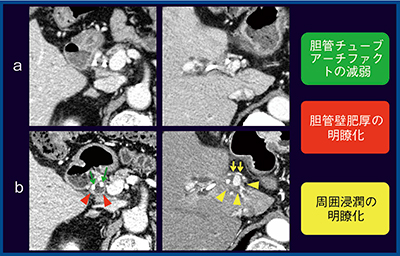

●症例3:肝門部領域胆管がん,ERBD後

図4は,70歳代,男性の肝門部領域胆管がん,内視鏡的逆行性胆道ドレナージ(ERBD)後である。ERBD後は,胆管チューブのアーチファクトにより評価が困難になるが,Aquilion Precision(図4 b)ではアーチファクトが減弱しており,胆管壁の肥厚を確認できる。他部位の浸潤の描出能もMDCT(図4 a)より向上しており,高い精度での評価が可能になる。

図4 症例3:肝門部領域胆管がん,ERBD後(70歳代,男性)

a:MDCT(1mm) b:Aquilion Precision(1mm)